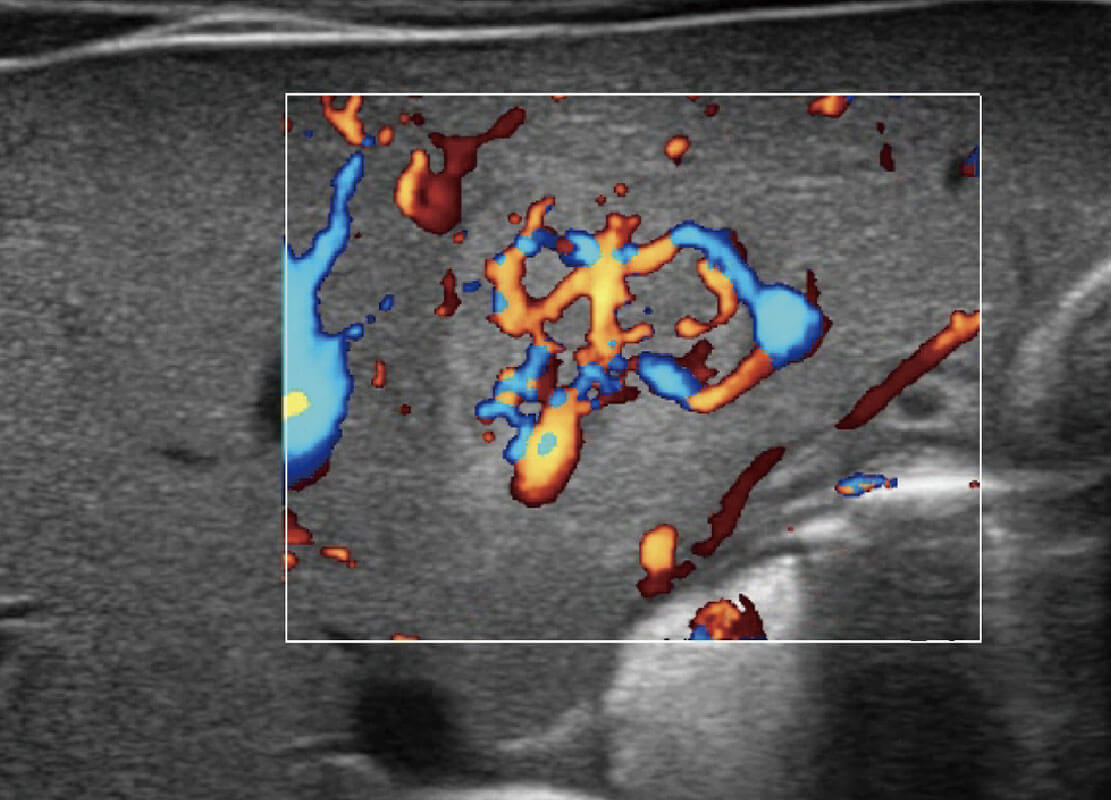

P60搭载宽频带线阵探头、宽景成像、弹性成像技术,为您提供乳腺应用方案。P60支持高频相控阵探头、线阵探头、腹部高频探头、腹部微凸探头等,丰富的探头群搭载敏感的彩色血流成像,适用于新生儿多种脏器检测要求,满足新生儿筛查需求。

乳腺导管癌

乳腺癌显微血流